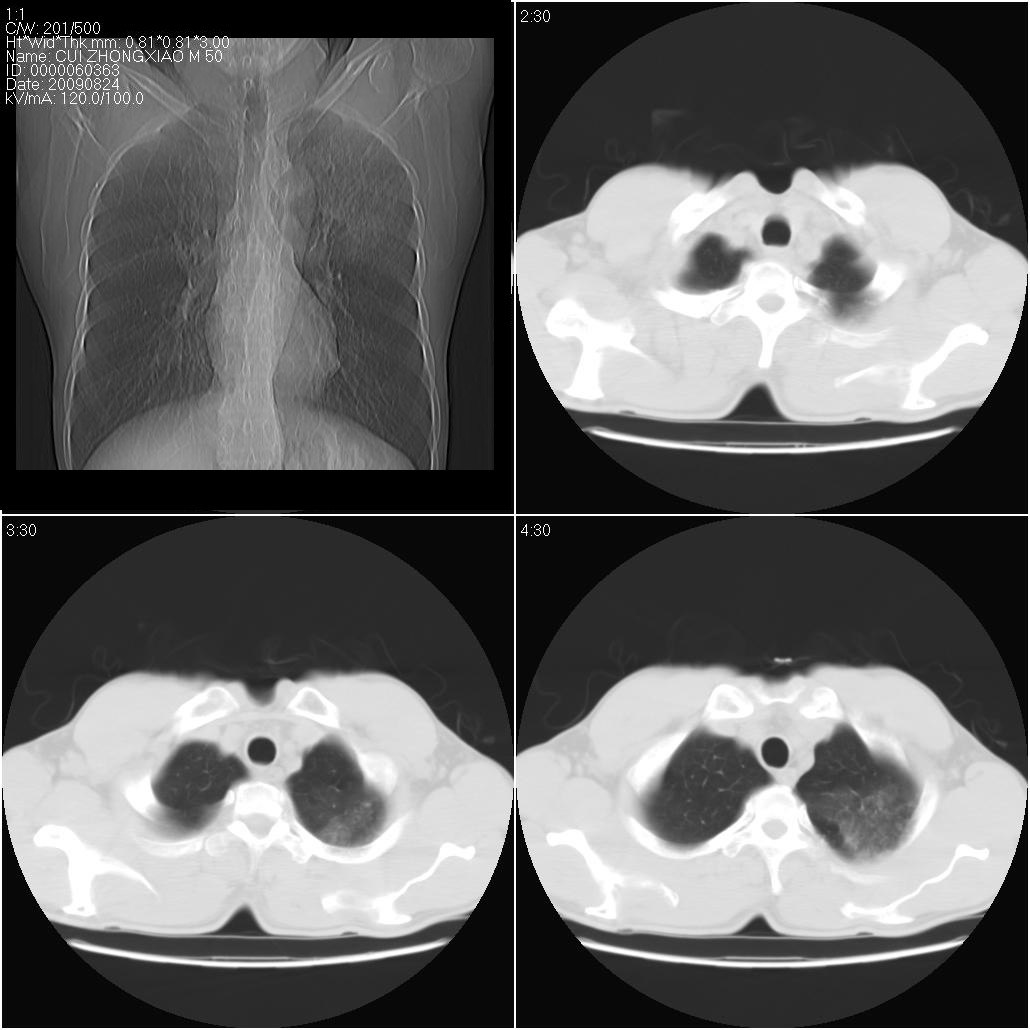

标题: CT21851:男性,50岁。间断性咳嗽半年。 [打印本页]

标题: CT21851:男性,50岁。间断性咳嗽半年。

肺泡蛋白沉着症

左侧感染!不排除局限性肺泡蛋白沉着症!

磨玻璃样改变(左肺及右肺上叶前段),边缘模糊,考虑炎症,建议严格抗炎治疗后复查除外肺泡蛋白沉积症或肺泡出血(病人有咯血吗) 肺泡癌.

肝左叶肝内胆管扩张,进一步检查.

双肺磨玻璃征改变。。。支持楼上

考虑以感染性病变,以结核可能性大,建议治疗后复查。